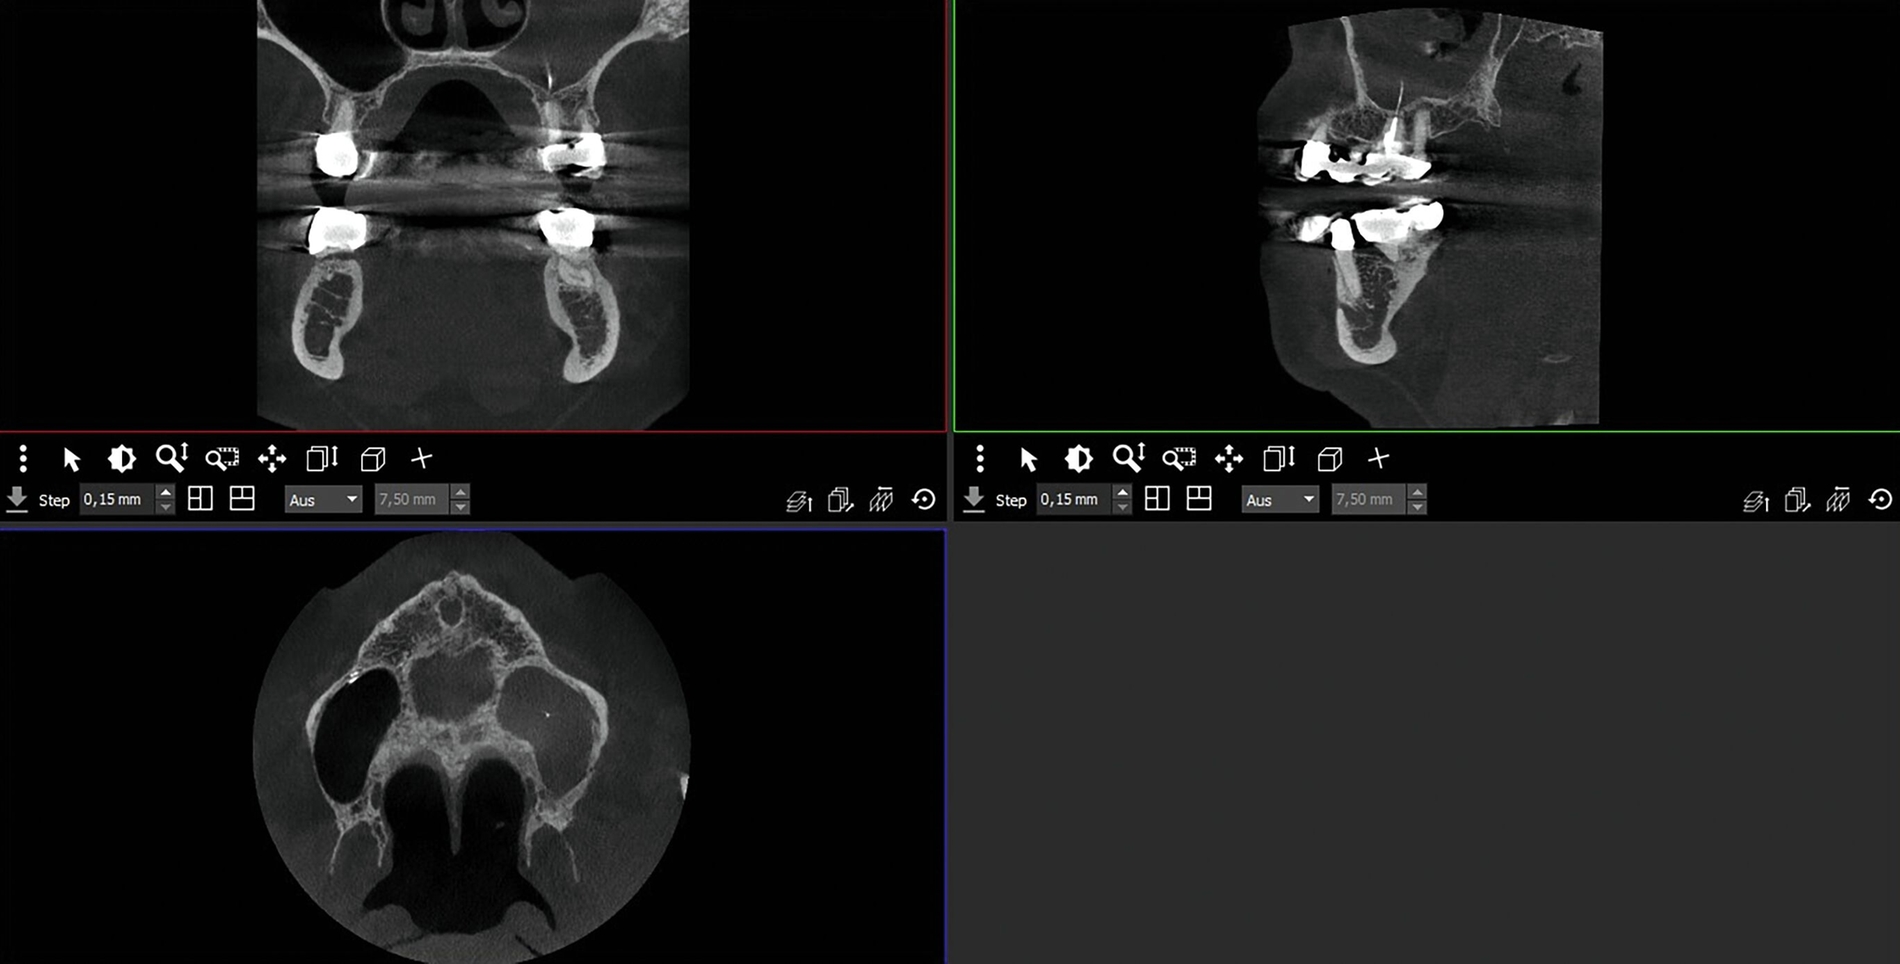

Bei der erneuten Vorstellung in der HNO-Abteilung etwa ein Jahr später berichtete die Patientin über eine seit Monaten bestehende Schwellung prämaxillär links sowie gelegentliche gelbliche Rhinorrhoe. Sie hatte zunächst eine niedergelassene HNO-Kollegin konsultiert, die eine DVT-Untersuchung durchführte, bei der eine Verschattung des linken Sinus maxillaris, verursacht durch eine überstopfte palatinale Wurzelfüllung am Zahn 26, nachgewiesen wurde (Abbildung 2).

Die Guttapercha-Füllung ragte dabei 7,2 mm in den Sinus maxillaris hinein. Die von der HNO-Ärztin veranlasste Begutachtung der DVT-Bilder durch einen niedergelassenen Zahnarzt ergab laut dessen Beurteilung keinen zahnärztlichen Handlungsbedarf. Bei bestehender Beschwerdesymptomatik (wie beschrieben) wurde die endoskopische Kieferhöhlenrevision links in Intubationsnarkose durchgeführt.

Hier wurde, neben einer klinischen Untersuchung, eine radiologische Diagnostik mittels OPG und DVT durchgeführt (Abbildung 3). Im Ergebnis manifestierte sich der dringende Verdacht, dass die überpresste Wurzelfüllung (Guttapercha-Stift/Sealer) die chronifizierte Pilzinfektion ausgelöst und unterhalten hatte. Daher wurde entschieden, den Zahn 26 zu extrahieren und gleichzeitig das überpresste Wurzelfüllmaterial zu entfernen.